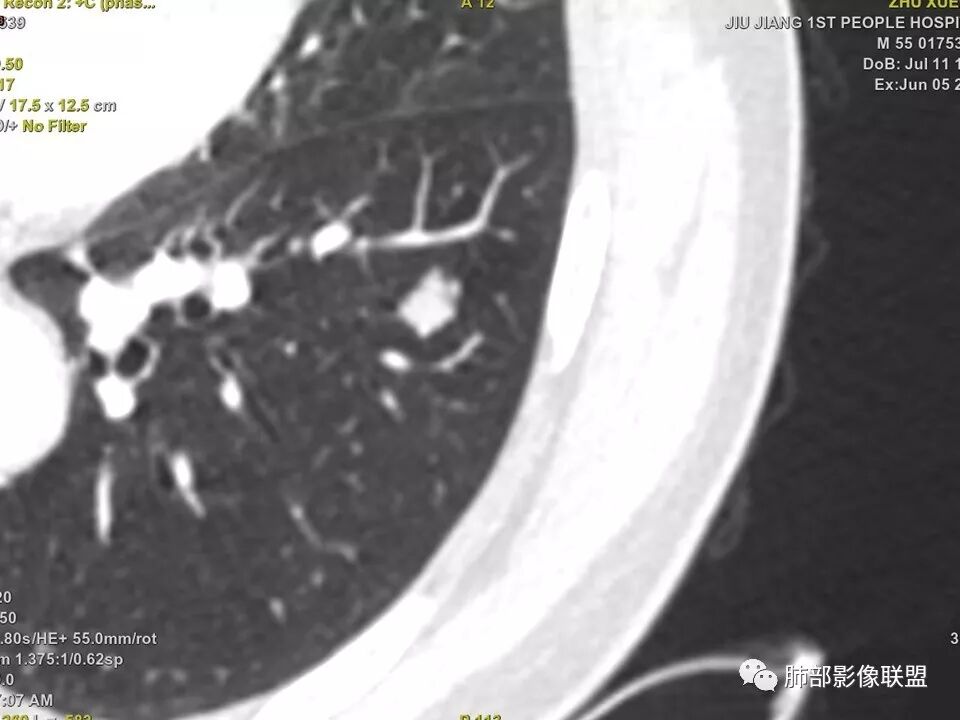

中年男性,左肺下叶不规则实性结节,有分叶及棘状凸起,支气管截断,轻度不均匀强化,考虑鳞癌,鉴别炎性肉芽肿。

实性结节,深分叶,支气管截断,考虑腺癌。只是强化有点低。鉴别:肉芽肿病变。

左肺下叶前内基底段结节 深分叶和脐凹 表面部分膨隆 部分收缩 支气管截断 轻度强化 中央有坏死 考虑鳞癌 鉴别炎性结节

病灶多结节融合,有分叶,也支气管截断,有细小血管连接,考虑恶性结节,周围型肺癌。

病灶部分平直丶内收,有脂肪密度,不强化支持错构瘤。部分病灶有结节堆积感,分叶,与支气管、肺动脉关系密切,需鉴别腺癌。不强化进一步结核结节。

左肺下叶前基底段结节,病灶边缘分叶,边缘平直,u型征,可见气管截断,增强可见病灶边缘血管,平扫ct值低,轻度强化。考虑良性病变。

典型CT特征包括:(1)圆形或椭圆形边界清楚的病灶。(2)大小1~4cm,有轻微分叶改变。(3)较均匀的软组织影,多伴有钙化。(4)无毛刺,卫星灶及肺门或纵隔淋巴结肿大。(5)CT增强扫描无强化或轻度强化,其强化可能与软骨瘤间质中的薄壁血管或周围慢性炎症反应有关。